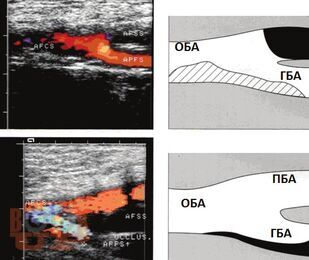

В монографии показаны ближайшие и отдаленные результаты бедренно-подколенного шунтирования в зависимости от вида трансплантата; представлена технология медицинской реабилитации пациентов. Особое внимание уделено послеоперационным осложнениям и методике лечения больных с окклюзионным поражением бедренно-подколенного сегмента.